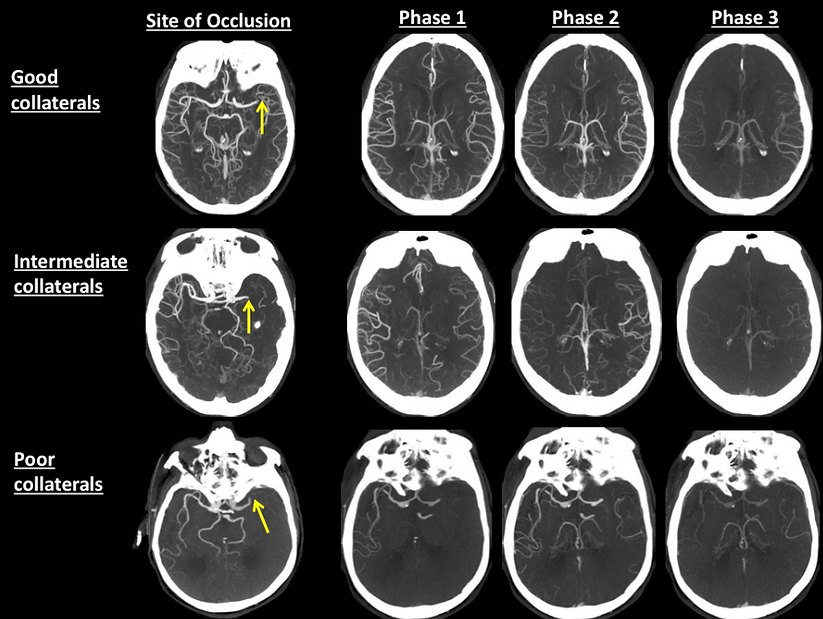

Quantification du niveau de collatérales